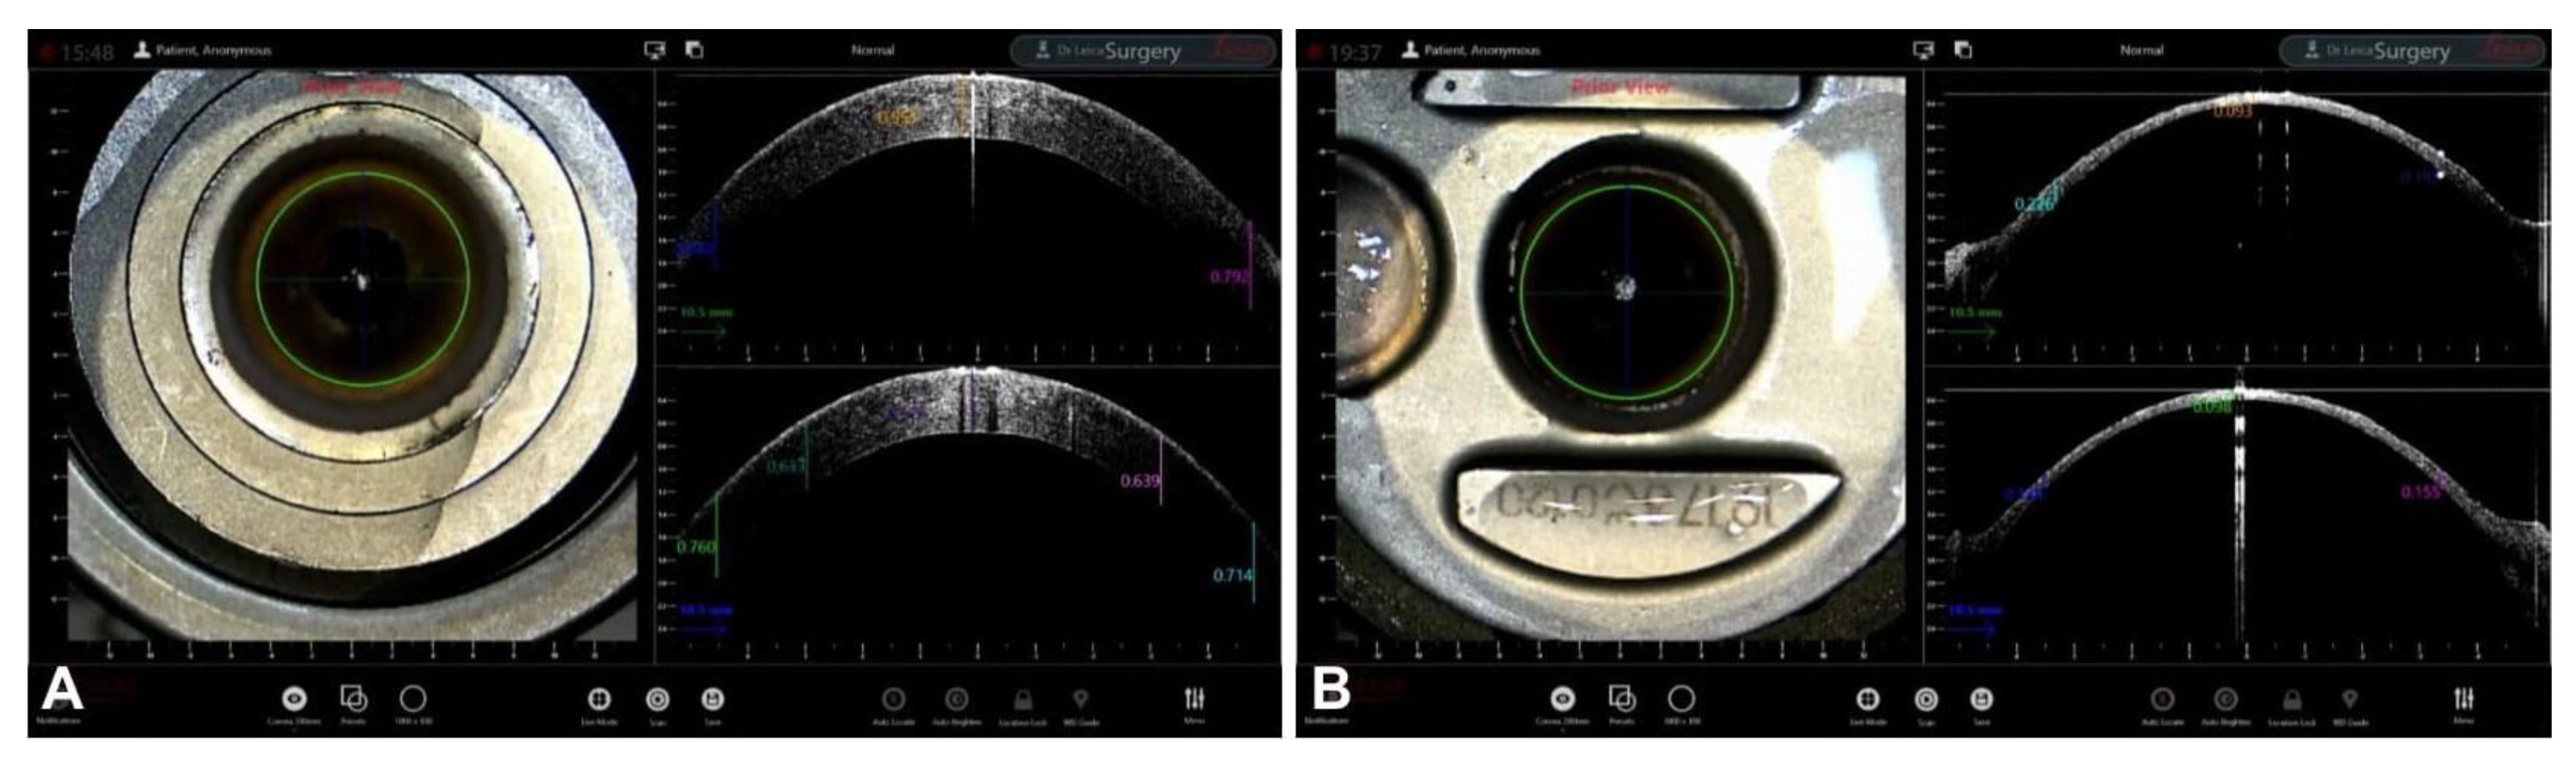

Guiding Big-Bubble Deep Anterior Lamellar Keratoplasty (BB-DALK)

4. Guiding Ultra-Thin Descemet Stripping Automated Endothelial Keratoplasy

- Busin, M.; Albè, E. Does thickness matter: Ultrathin Descemet stripping automated endothelial keratoplasty. Curr. Opin. Ophthalmol. 2014, 25, 312–318. [Google Scholar] [CrossRef] [PubMed]

- Fenech, M.T.; Coco, G.; Pagano, L.; Gadhvi, K.A.; Titley, M.; Levis, H.J.; Parekh, M.; Kaye, S.B.; Romano, V. Thinning rate over 24 months in ultrathin DSAEK. Eye 2022, 37, 655–659. [Google Scholar] [CrossRef]

- Romano, V.; Steger, B.; Myneni, J.; Batterbury, M.; Willoughby, C.E.; Kaye, S.B. Preparation of ultrathin grafts for Descemet-stripping endothelial keratoplasty with a single microkeratome pass. J. Cataract. Refract. Surg. 2017, 43, 12–15. [Google Scholar] [CrossRef] [PubMed]

- Kobayashi, A.; Yokogawa, H.; Mori, N.; Sugiyama, K. Visualization of precut DSAEK and pre-stripped DMEK donor corneas by intraoperative optical coherence tomography using the RESCAN 700. BMC Ophthalmol. 2016, 16, 135. [Google Scholar] [CrossRef]

- Agarwal, R.; Shakarwal, C.; Sharma, N.; Titiyal, J. Intraoperative optical coherence tomography-guided donor corneal tissue assessment and preparation. Indian J. Ophthalmol. 2022, 70, 3496. [Google Scholar] [CrossRef]

- Ruzza, A.; Parekh, M.; Avoni, L.; Wojcik, G.; Ferrari, S.; Desneux, L.; Ponzin, D.; Levis, H.J.; Romano, V. Ultra-thin DSAEK using an innovative artificial anterior chamber pressuriser: A proof-of-concept study. Graefe’s Arch. Clin. Exp. Ophthalmol. 2021, 259, 1871–1877. [Google Scholar] [CrossRef]

- Pasricha, N.D.; Shieh, C.; Carrasco-Zevallos, O.; Keller, B.; Izatt, J.A.; Toth, C.A.; Kuo, A.N. Real-Time Microscope-Integrated OCT to Improve Visualization in DSAEK for Advanced Bullous Keratopathy. Cornea 2015, 34, 1606–1610. [Google Scholar] [CrossRef] [PubMed]

- Steverink, J.G.; Wisse, R.P.L. Intraoperative optical coherence tomography in descemet stripping automated endothelial keratoplasty: Pilot experiences. Int. Ophthalmol. 2016, 37, 939–944. [Google Scholar] [CrossRef] [PubMed]

- Nowinska, A.; Wylegala, E.; Wroblewska-Czajka, E.; Janiszewska, D. Donor disc attachment assessment with intraoperative spectral optical coherence tomography during descemet stripping automated endothelial keratoplasty. Indian J. Ophthalmol. 2013, 61, 511–513. [Google Scholar] [CrossRef] [PubMed]

- Juthani, V.V.; Goshe, J.M.; Srivastava, S.K.; Ehlers, J.P. Association Between Transient Interface Fluid on Intraoperative OCT and Textural Interface Opacity After DSAEK Surgery in the PIONEER Study. Cornea 2014, 33, 887–892. [Google Scholar] [CrossRef]

- Hallahan, K.M.; Cost, B.; Goshe, J.M.; Dupps, W.J.; Srivastava, S.K.; Ehlers, J.P. Intraoperative Interface Fluid Dynamics and Clinical Outcomes for Intraoperative Optical Coherence Tomography–Assisted Descemet Stripping Automated Endothelial Keratoplasty From the PIONEER Study. Am. J. Ophthalmol. 2016, 173, 16–22. [Google Scholar] [CrossRef]

- Yokogawa, H.; Kobayashi, A.; Mori, N.; Nishino, T.; Nozaki, H.; Sugiyama, K. Intraoperative optical coherence tomography-guided nanothin Descemet stripping automated endothelial keratoplasty in a patient with a remarkably thickened cornea. Am. J. Ophthalmol. Case Rep. 2022, 25, 101414. [Google Scholar] [CrossRef]